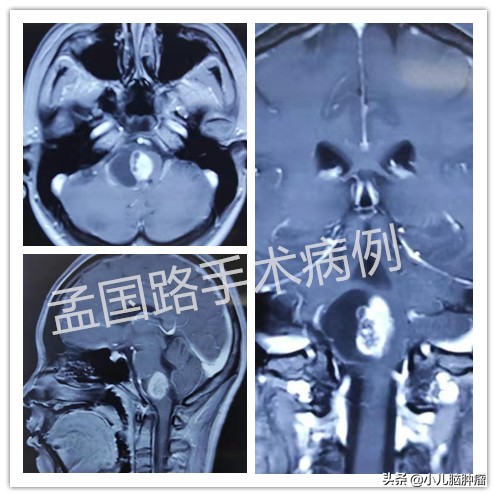

这个肿瘤生长在脑干的延髓部位,相对于延髓来说,还是比较大的。脑干分为三部分:中脑、桥脑和延髓。按由上到下的顺序排列。延髓向下就是脊髓了,就出了头颅来到椎管了。延髓是脑干最细的部分,但是功能非常重要。不但有重要的运动和感觉神经纤维通过,还有心跳呼吸中枢,并存在很多神经核团,与吞咽、伸舌等咽喉肌肉的运动相关。

这个肿瘤磁共振强化比较明显,所谓强化明显,就是做磁共振时,静脉注射增强剂后,肿瘤会变白。这种情况,要做其他检查,看看是不是脑干血管网状细胞瘤。由于这种肿瘤切除方法与胶质瘤不同,最好术前就做好相应准备。这个孩子手术前做了脑血管造影,不是血管网状细胞瘤。